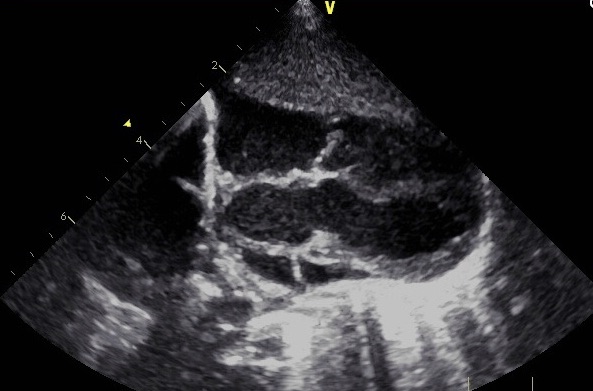

Echocardiography findings showed pulmonary atresia with ventricular septal defect (PA-VSD) and major aortopulmonary collateral arteries (MAPCAs) (Figure 1). The interatrial septum was floppy and aneurysmal with a large secundum atrial septal defect (ASD) with predominantly left-to-right shunting. Mild tricuspid regurgitation was noted, with a possible association to small left ventricle to right atrium shunt, as well as mild right ventricle enlargement and normal left ventricle size. The pulmonary valve was atretic with hypoplastic, confluent main and branch pulmonary arteries, fed by multiple aortopulmonary collaterals. Furthermore, indeterminate arch sidedness with large collaterals was seen coming off the descending aorta.

Figure 1. Echocardiogram showing the presence of PA-VSD.